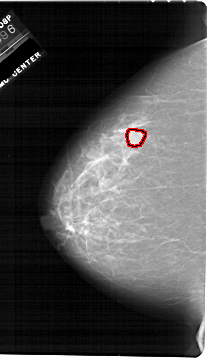

A_1763_1.LEFT_MLO

LEFT_MLO LINES 6871 PIXELS_PER_LINE 4171 BITS_PER_PIXEL 12 RESOLUTION 43.5 OVERLAY

FILE: A_1763_1.LEFT_MLO.OVERLAY

TOTAL_ABNORMALITIES 1

ABNORMALITY 1

LESION_TYPE MASS SHAPE OVAL MARGINS ILL_DEFINED

ASSESSMENT 4

SUBTLETY 3

PATHOLOGY BENIGN

TOTAL_OUTLINES 1

BOUNDARY